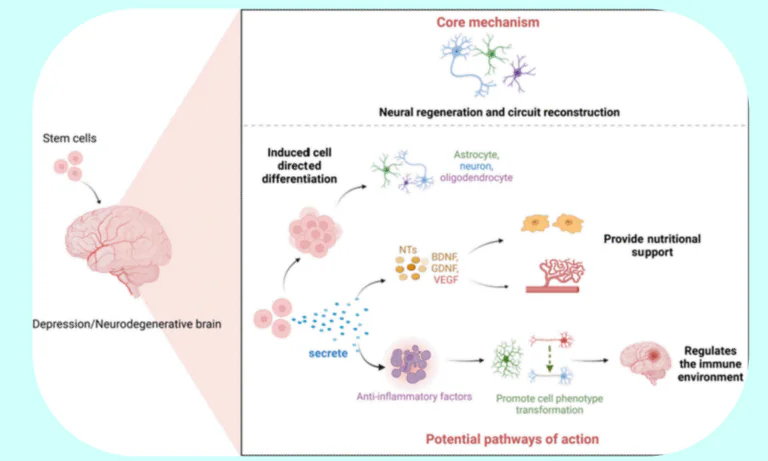

Neurodegenerative

Stem cells may repair damaged neuron connections.

How Stem Cell Therapy May Help

Stem cell therapy may help support brain cell protection and reduce inflammation. It may enhance neural connectivity and improve cognitive function and quality of life.

How Stem Cell Therapy May Help

Stem cell therapy may support dopamine-producing neurons and reduce inflammation in the brain. It may help improve motor function and coordination when combined with medications and physiotherapy.